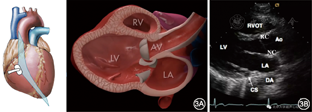

胸骨旁左心室长轴切面相当于将左心室纵切,解剖示意图和超声图像见图3,此切面可观察到:①心腔结构:左心房、左心室、右心室流出道;②主动脉根部和部分升主动脉;③二尖瓣和主动脉瓣;④室间隔与左心室后壁厚度及运动幅度;⑤心包;⑥冠状静脉窦。

注:LA左心房;LV左心室;RV右心室;AV主动脉瓣;RVOT右心室流出道;Ao主动脉;RC主动脉右冠瓣;NC主动脉无冠瓣;CS冠状静脉窦;DA降主动脉

注:RV右心室;LV左心室;AV主动脉瓣口流速;MV二尖瓣;PE心包积液;LA左心房